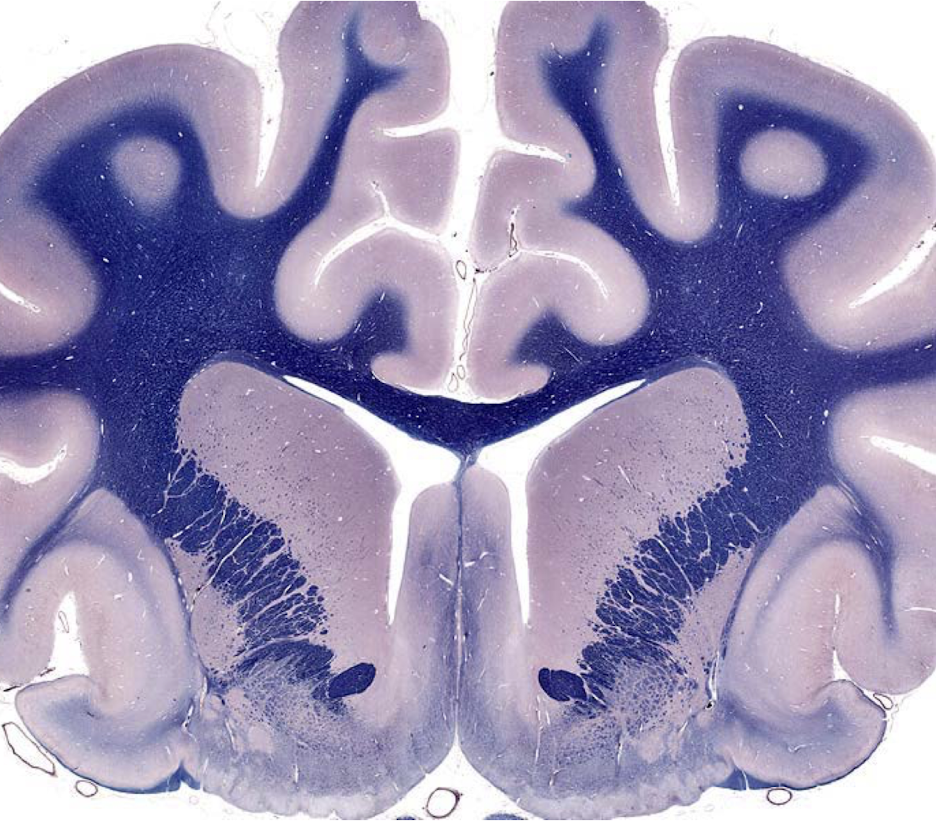

what section of the brain is shown?

rostral medulla

- closed 4th ventricle

- trapezoid body

- pyramids